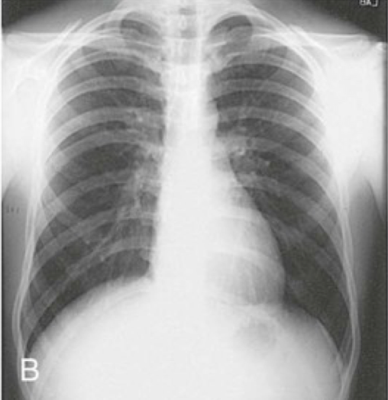

Question 10

Question

Identify the body habitus.

Answer

• Asthenic

• Sthenic

• Hyposthenic

• Hypersthenic